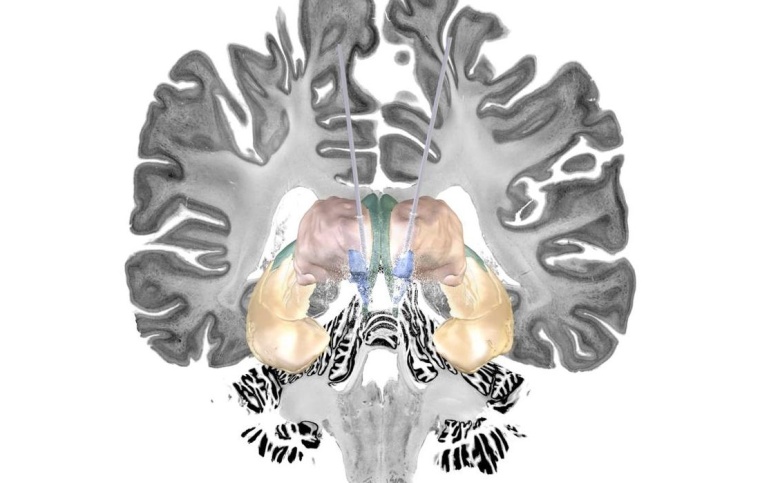

Die Forschungsgruppe um Prof. Horn hat sich darauf spezialisiert, hochaufgelöste Bilder des Gehirns, die mithilfe der Kernspintomographie aufgenommen werden, zu analysieren und in Kombination mit Computermodellen die optimalen Stimulationspunkte für eine THS im Gehirn hochpräzise aufzuspüren. „Eine besondere Herausforderung dabei ist: Jedes Gehirn ist anders. Und das spielt bei der Implantierung der Elektroden eine große Rolle“, sagt Prof. Horn. „Liegt man nur wenige Millimeter daneben, bleibt der erwartete Effekt unter Umständen aus.“ Auch bei dem Großteil der Studienteilnehmenden war das der Fall. Das Forschungsteam um Prof. Horn konnte aber bei denjenigen Alzheimer-Patienten, bei denen die THS anschlug, die genaue Position der Elektroden anhand der Bilddaten im Nachgang exakt bestimmen. „Sie liegt an einer Zweigstelle zwischen zwei Nervenfaserbündeln – dem Fornix und der Stria terminalis –, die tiefgelegene Hirnregionen miteinander verbinden. Beide Strukturen werden mit der Gedächtnisfunktion in Verbindung gebracht“, erklärt der Neurowissenschaftler.